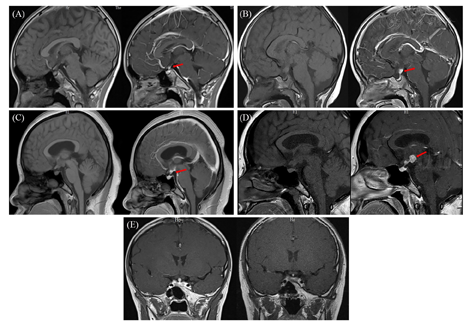

注:(A)病例1(初诊时),垂体柄上部局限性增粗,增强后明显强化,垂体后叶高信号未见显示;(B)病例2(初诊时),垂体柄增粗并结节状强化明显,垂体后叶高信号未见显示;(C)病例3(初诊时),垂体柄根部及第三脑室周围病变,增强后明显强化,垂体后叶高信号未见显示;(D)病例3(9个月后复诊时),垂体柄根部及第三脑室周围病变,范围较前扩大,垂体后叶高信号可见;(E)病例1治疗前、治疗1年后,垂体柄增粗较前缓解

病例1:患儿男性,11岁5个月。2019年2月出现口干、多饮、多尿,饮水量达4 L/d,尿量与饮水量相当,夜尿2~3次,伴乏力、食欲下降、偏好冷饮水果,无头痛、视物模糊、视野缺损。入住本院后,查血常规、肝功能、肾功能、血电解质无异常,24 h尿量4.5 L,血渗透压327 mmol/L(参考范围280~310 mmol/L,下同)、尿渗透压129 mmol/L(40~1 200 mmol/L)、尿比重1.005(1.01~1.03)。禁饮试验过程中血钠水平升至164 mmol/L,终止试验。应用弥凝片治疗,症状明显改善。甲状腺功能:游离三碘甲状腺原氨酸(FT3)5.12 pmol/L(3.28~6.47 pmol/L)、游离甲状腺素(FT4)14.76 pmol/L(7.9~18.4 pmol/L)、促甲状腺激素(TSH)1.57 μIU/mL(0.34~5.6 μIU/mL)。甲状旁腺激素(PTH)28.24 pg/mL(15~65 pg/mL)。促肾上腺皮质激素(ACTH)水平8:00为44.3 pg/mL(7.0~61 pg/mL)、16:00为25.2 pg/mL。皮质醇水平:8:00为25.2 μg/dL(7~27 μg/dL)、16:00为17.4 μg/dL。催乳素29.9 ng/mL(3.5~19.4 ng/mL)、生长激素1.63 ng/mL(0.06~5 ng/mL)、胰岛素样生长因子1(IGF-1)水平160.7 ng/mL(117~329 ng/mL)。垂体磁共振成像(MRI):垂体柄上部局限性增粗,增强后明显强化,垂体后叶高信号未见显示,诊断为"中枢性尿崩症"(图1A)。甲状腺彩超:右侧叶中下部实性低回声结节,大小约25 mm×9 mm×10 mm,边界清,形态不规则;左侧叶中下级背侧可探及一大小约18.7 mm×9.8 mm×8.7 mm实性低回声结节,边界清,形态规则;双侧锁骨上窝均可及一实性结节,右侧约13 mm×6 mm,左侧约19.8 mm×13 mm,边界清,形态不规则。行甲状腺右侧叶结节细针穿刺活检术,病理诊断为朗格汉斯细胞组织细胞增生症(Langerhans cell histiocytosis, LCH;图2),免疫组织化学示CD68(部分+)、S-100(+)、CD1a(+)、Langerin(+)、Ki-67(60%+),实时荧光PCR及DNA测序未发现BRAF基因V600E突变。彩超:肝脏和脾脏无异常。肺部计算机断层扫描(CT):未见异常。全身骨显像:各部位骨骼未见异常放射性浓聚或稀疏区。正电子发射计算机断层显像(PET-CT):甲状腺双叶低密度结节代谢活跃(标准摄取最大值:12.9),符合LCH;右颈Ⅳ区肿大淋巴结代谢稍活跃(标准摄取最大值:3.4),前纵隔片状软组织密度影代谢活跃(标准摄取最大值:10.2),考虑病变累及淋巴结及胸腺。

病例2:患儿女性,6岁11个月。2岁3个月时出现烦渴、多饮、多尿,日饮水量约3 L,尿量约3 L,夜尿4~5次,伴饮食量下降(约1/3)和生长停滞。当地医院查头颅MRI:(1)垂体柄漏斗部增粗;(2)双侧颈部多发淋巴结肿大,诊断为"中枢性尿崩症"。口服弥凝片治疗,上述症状改善。2岁11个月时至本院查血常规、肝功能、肾功能、血电解质无异常。血渗透压301 mmol/L、尿渗透压166 mmol/L、尿比重1.005。甲状腺功能:FT34.70 pmol/L、FT410.84 pmol/L、TSH 2.36 μIU/mL。ACTH-皮质醇节律示ACTH水平8:00为12.1 pg/mL(7.2~63.3 pg/mL)、16:00为7.6 pg/mL,皮质醇水平8:00为481 ng/mL(171~536 ng/mL)、16:00为226 ng/mL。生长激素激发试验(左旋多巴):0 min为0.4 ng/mL、15 min为0.6 ng/mL、30 min为0.5 ng/mL、60 min为0.5 ng/mL、90 min为0.5 ng/mL。催乳素38.32 ng/mL(5.2~26.5 ng/mL);血β绒毛膜促性腺激素<0.1 mIU/mL(0~5 mIU/mL)、脑脊液β绒毛膜促性腺激素0.96 mIU/mL。复查垂体MRI(图1B):垂体柄增粗并结节状强化明显,大小约5.5 mm×5.8 mm×10.1 mm,考虑生殖细胞瘤、LCH、炎症;垂体后叶高信号未见显示。头颅X线片:未见明显异常。彩超:甲状腺未见异常;颈部多发肿大淋巴结、皮髓质分界清晰;肝脏和脾脏未见异常。行左侧颈部肿大淋巴结穿刺活检术,病理结果示较多成熟淋巴细胞、未见明确恶性病变。建议患儿家属进一步行垂体柄活检术,家属拒绝。5岁9个月时至外院查头颅MRI示鞍区结节样等信号影,增强后病变明显强化,大小约12 mm×8 mm×11 mm,行脑立体定位活组织检查术,病理示LCH,免疫组织化学示CD68(+)、S-100(+)、Langerin(+)、CD1a(少数+)、Ki-67(+)。

病例3:患者女性,30岁。2017年10月出现口渴、多饮、多尿,日饮水量5~6 L,尿量约5 L,夜尿3~4次,伴乏力、月经周期延长、月经量减少,无头痛、视物模糊、视野缺损,食欲正常,体重半年增加10 kg。患者20岁、22岁时分别行剖腹产分娩1子1女。入院后查血常规、肝功能、肾功能、血电解质无异常。血渗透压321 mmol/L(275~310 mmol/L)、尿渗透压150 mmol/L、尿比重1.005。甲状腺功能:FT34.88 pmol/L、FT46.25 pmol/L、TSH 0.47 μIU/mL。PTH:25.41 pg/mL。ACTH-皮质醇节律示ACTH水平8:00为30.5 pg/mL、16:00为28.0 pg/mL,皮质醇水平8:00为4.47 μg/dL、16:00为2.85 μg/dL,24 h尿(尿量5.2 L)游离皮质醇水平73 nmol/d(73~372 nmol/d)。生长激素<0.05 ng/mL,IGF-1水平199.1 ng/mL。性激素六项:卵泡刺激素(FSH)2.6 mIU/mL(3.03~8.08 mIU/mL)、促黄体生成素(LH)0.13 mIU/mL(2.39~6.60 mIU/mL)、雌二醇11.0 pg/mL(21~251 pg/mL)、孕酮<0.1 ng/mL(<0.1~0.3 ng/mL)、睾酮<0.13 ng/mL(0.11~0.57 ng/mL)。催乳素143.22 ng/mL;血β绒毛膜促性腺激素<0.1 mIU/mL。行禁饮加压素试验(+)。垂体MRI(图1C):垂体柄漏斗部及三脑室周围病变,增强后明显强化,考虑LCH、炎症性疾病、结节病;垂体后叶高信号未见显示。彩超:甲状腺未见异常,浅表淋巴结未见异常肿大,肝脏和脾脏无异常。肺部CT:未见异常。腰椎穿刺术失败,未能检测脑脊液β绒毛膜促性腺激素水平和病理细胞。建议患者行鞍区病变活检术,患者拒绝,给予糖皮质激素、左甲状腺素钠片(优甲乐)、醋酸去氨加压素片(弥凝片)替代治疗后出院。2018年6月至外院就诊,诊断为"垂体炎",予以甲泼尼龙(12 mg/d)口服,后调整为泼尼松(20 mg/d),症状无改善,渐出现继发性闭经。2019年1月至本院复查垂体MRI(图1D):垂体柄漏斗部及三脑室周围病变,范围较2018年4月扩大,垂体后叶高信号未见显示。2019年4月至外院行脑立体定位活组织检查术,病理示LCH,免疫组化S-100()、Langerin()、CD1a()、CD68(+)、催乳素(-)、Ki-67指数约10%。

中枢神经系统中,LCH最常累及下丘脑-垂体区域,下丘脑因为血脑屏障作用较垂体少受累。下丘脑-垂体区域受累时最常见临床表现是中枢性尿崩症,中枢性尿崩症在LCH中发生率为5%~29.6%,其中不到5%的患者会同时发生神经垂体和腺垂体功能减退症[7,8]。本报道3例患者中,病例1单独出现中枢性尿崩症;病例2除了中枢性尿崩症外,还发生了生长激素缺乏症;病例3下丘脑和垂体均被累及,发生了中枢性尿崩症、继发性闭经、继发性甲状腺功能减退、继发性肾上腺皮质功能减退和成人生长激素缺乏症,提示病变范围和临床症状密切相关。MRI具有较高的空间分辨率和很好的组织分辨率,是目前显示下丘脑-垂体柄及其周围结构的首选方法,以矢状和冠状增强显示效果最佳。国内黄文献等[9]的研究显示,13例儿童孤立性垂体LCH的MRI中,垂体后叶T1W1正常高信号均消失,11例垂体柄呈结节样或均匀增粗,2例漏斗部呈结节样增粗,动态增强扫描呈渐进性强化、直至明显强化。本研究报道的3例患者MRI表现与上述研究类似。在缺乏病史的情况下,大多数LCH患者中枢神经系统的影像学改变是非特异的,需要和Rathke囊肿、鞍区肿瘤(脑膜瘤、错构瘤、生殖细胞瘤)、垂体微腺瘤等进行鉴别。

病例1患儿:2019年3月开始规律行阿糖胞苷联合克拉屈滨方案,化疗9次后改为静推长春地辛+口服巯嘌呤方案。治疗1年后复诊,患儿尿崩症状未缓解,身高增加5 cm,第二性征未发育。查FSH 0.48 mIU/mL、LH<0.10 mIU/mL、睾酮<0.025 ng/mL;生长激素2.45 ng/mL,IGF-1水平337.2 ng/mL。彩超:甲状腺双侧叶多发囊性小结节(TI-RADS:2级),双侧颈部未见异常肿大淋巴结。垂体MRI:垂体柄局限性增粗较前缓解,垂体后叶高信号未见显示。